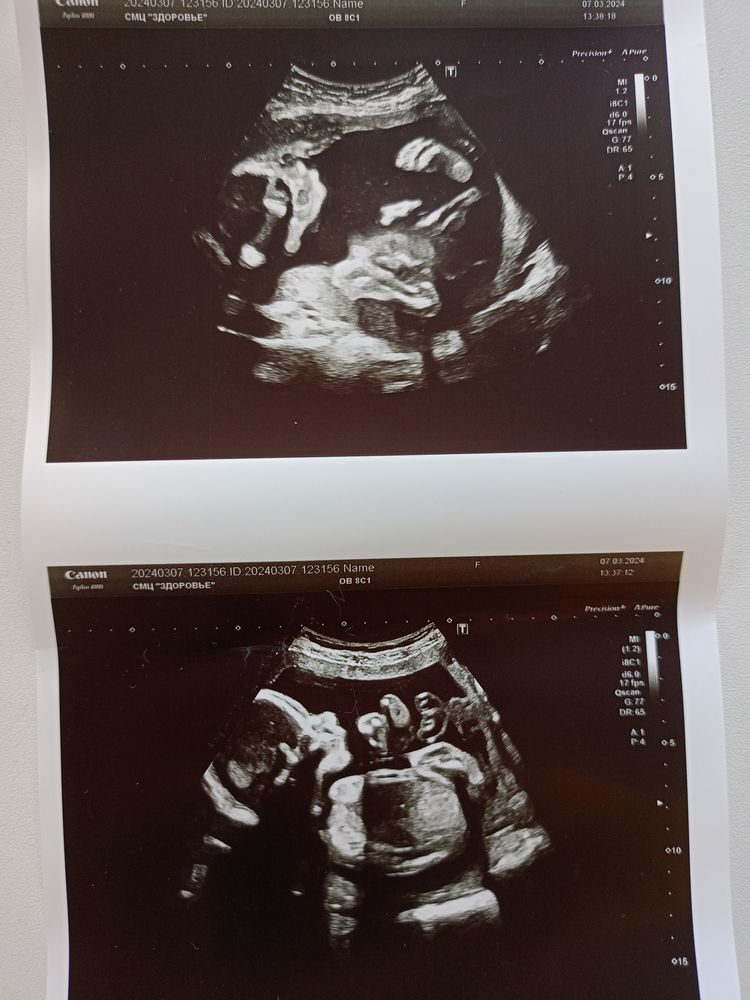

21 неделька. Наши будни

настя, для меня он непривычно большой 😅 Даже с двойней мне кажется в 21 неделю меньше был ну или такой же 🙈 Правда от той беременности почти ни одной фотографии животика нет. А вот с сыном что с первым, что с младшим вообще живота практически не было. Сейчас мне кажется такой живот из-за того, что малышка поперёк легла. Буквально в воскресенье ещё ничего не видно было (приезжали в гости толпа родственников - никто даже не заметил), а в понедельник он выкатился, что уже и одеждой не спрячешь.